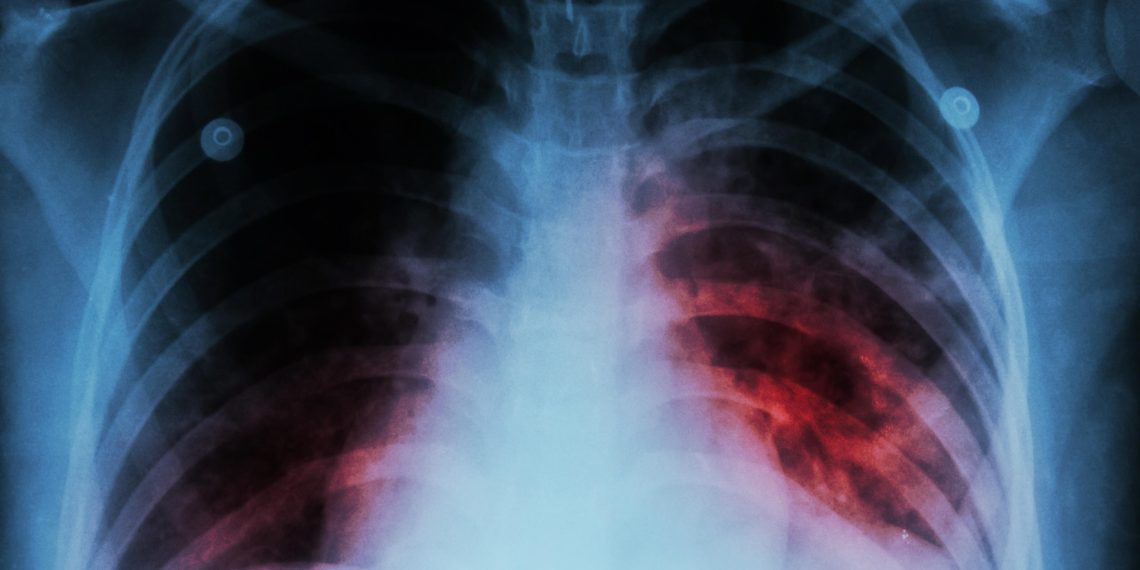

Las cifras de tuberculosis en Santander y Colombia son verdaderamente preocupantes. Según el Sistema Nacional de Vigilancia de Salud Pública SIVIGILA, en 2024 se registraron más de 35 mil casos de tuberculosis en el país, lo que representa un aumento del 25% en comparación con 2023.

Las preocupantes cifras la dieron a conocer este 10 de febrero Día Mundial de la Tuberculosis el Sistema Nacional de Salud, al indicar que el departamento de Santander fue el quinto más afectado con 1.391 casos en 2024, siendo Bucaramanga el municipio de mayor incidencia de tuberculosis, con 671 casos notificados. Le sigue Barrancabermeja, Floridablanca y Girón.

Lo más preocupante es que, en lo que va de 2025, Santander se ubica en el cuarto departamento más afectado, con 127 registros, de los cuales 78 son hombres y 49 son mujeres, la mayoría de los cuales viven en Bucaramanga.